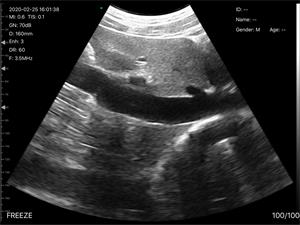

C3无线超声诊断仪

适用对象:

[ 猫、狗、牛、马、老鼠、异宠 ]

数字成像技术,清晰的图像,高性价比

无线连接,操作简单轻便,携带方便